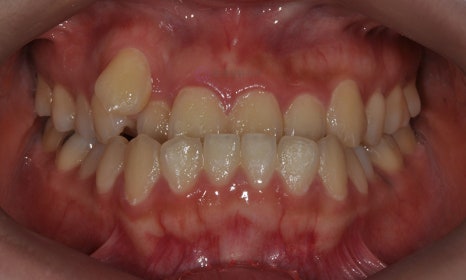

오늘은 주걱턱과 함께 덧니를 주소로 내원한 환자의 케이스를 살펴보도록 하겠습니다.

2017.12

본 환자는 오른쪽 송곳니가 나올 공간이 부족하여 드라큘라 이빨처럼 높게 맹출하였고(high canine), 왼쪽 두번째 작은 어금니는 아예 맹출할 공간이 부족하여 입천장으로 맹출해 있는 것을 볼 수 있습니다. 삐뚤빼뚤한 위턱 치아들에 비하여 아래 치아는 가지런한 편이었고, 어금니의 교합관계는 양호한 편이었습니다.